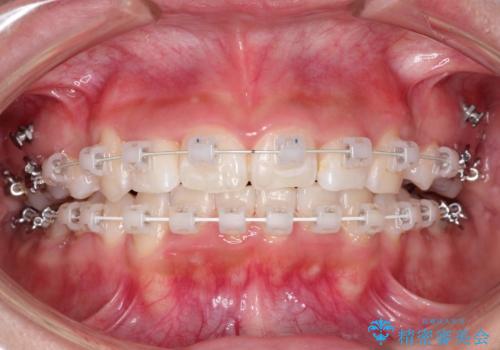

- 前歯のがたつきと出っ歯が気になるとのことで来院されました。

上顎の前から4番目の歯を両側合計2本抜歯して矯正することとなりました。

抜歯をして矯正をすることで、前歯を後方に移動させ、ガタガタを改善することができました。